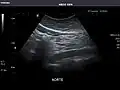

Aorta: Visualized portions normal in caliber, 16 x 15 mm.

Aorta